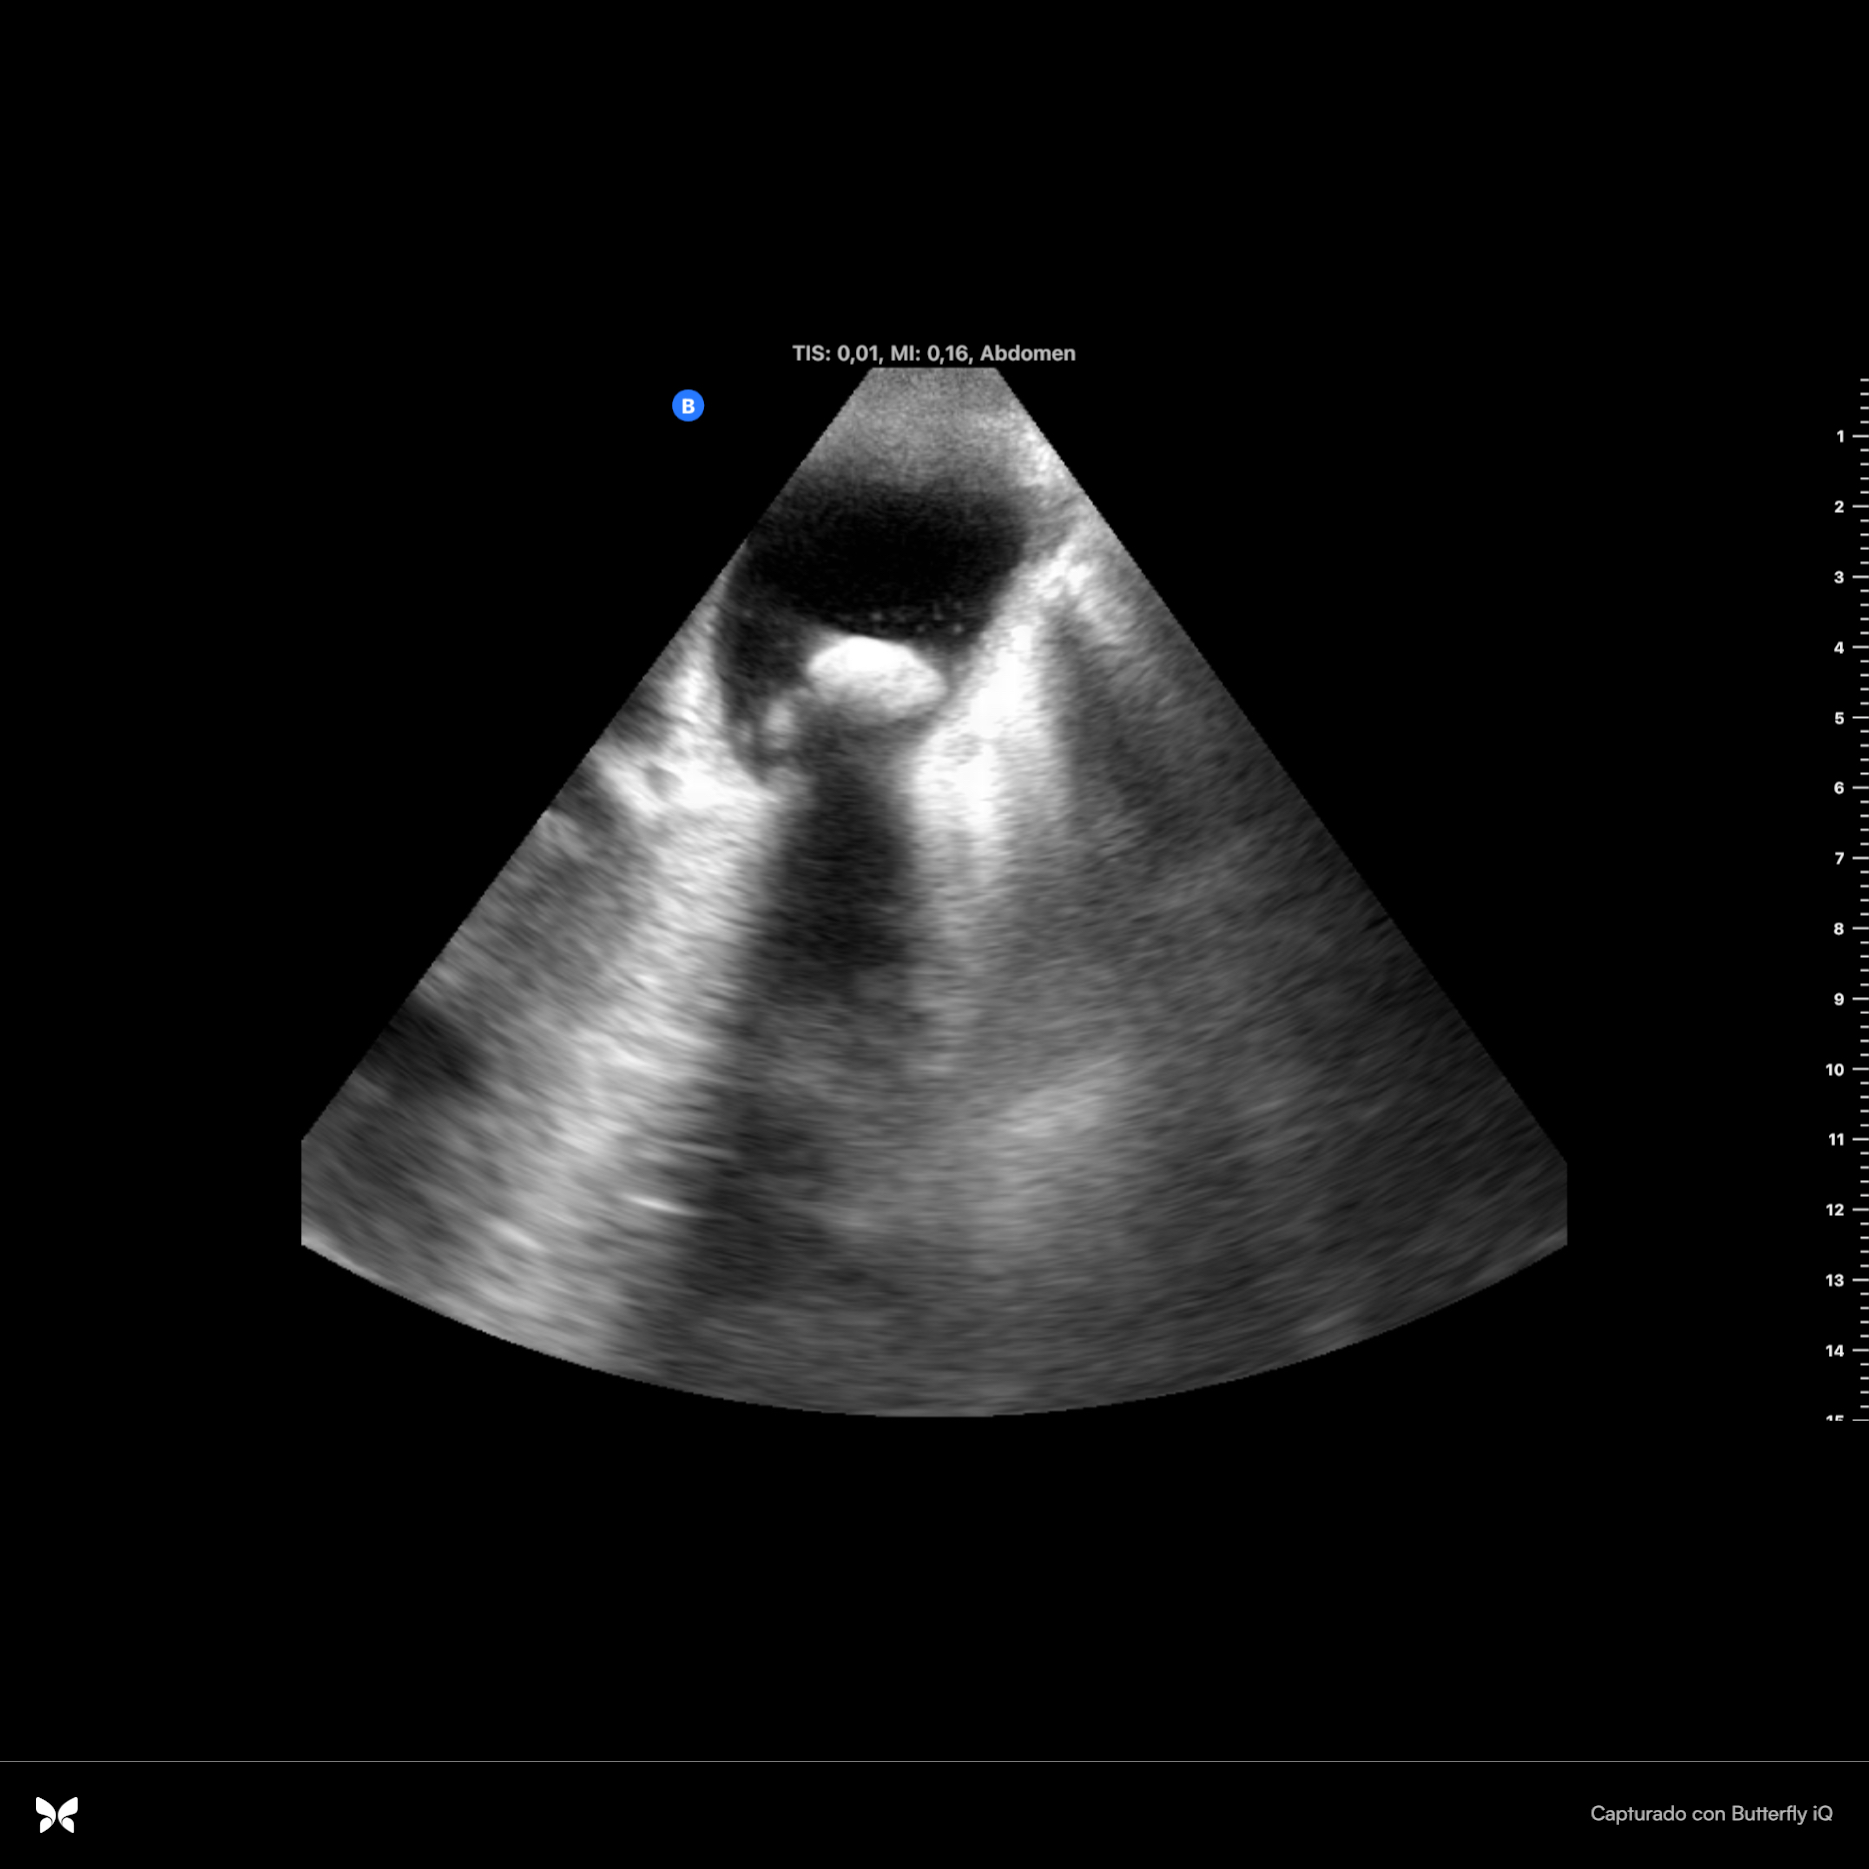

Se observan dos imágenes hiperecoicas en infundíbulo de vesícula que dejan sombra acústica posterior, una de ellas de 2 cm x 0.94 cm con aumento de grosor de vasos suprahepáticas. Parénquima hepático sin alteraciones. Se observa espacio anecoico superior al diafragma. Resto sin hallazgos.

En ecografía hospitalaria se observa claramente la dilatación de vía intra y extrahepática: colédoco con calibre de hasta 18 mm. Además se describen más hallazgos de insuficiencia cardíaca tales como líquido perivesicular y derrame plural derecho de espesor de hasta 7.5 cm y atelectasia del parénquima pulmonar.